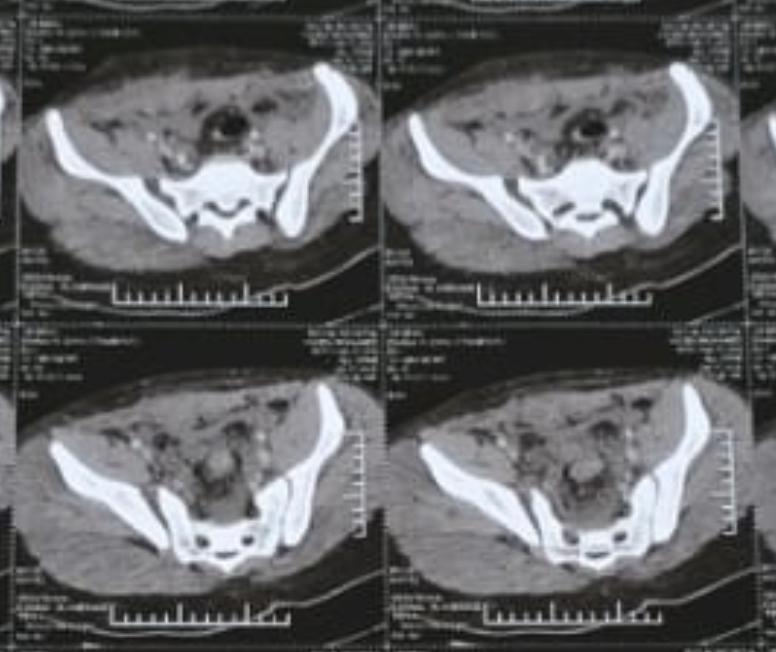

ياسين محمد أمين العمر:١٧ عامًا اصيب بكسر غير ثابت متفتت بالحوض يناير ٢٠٢٣